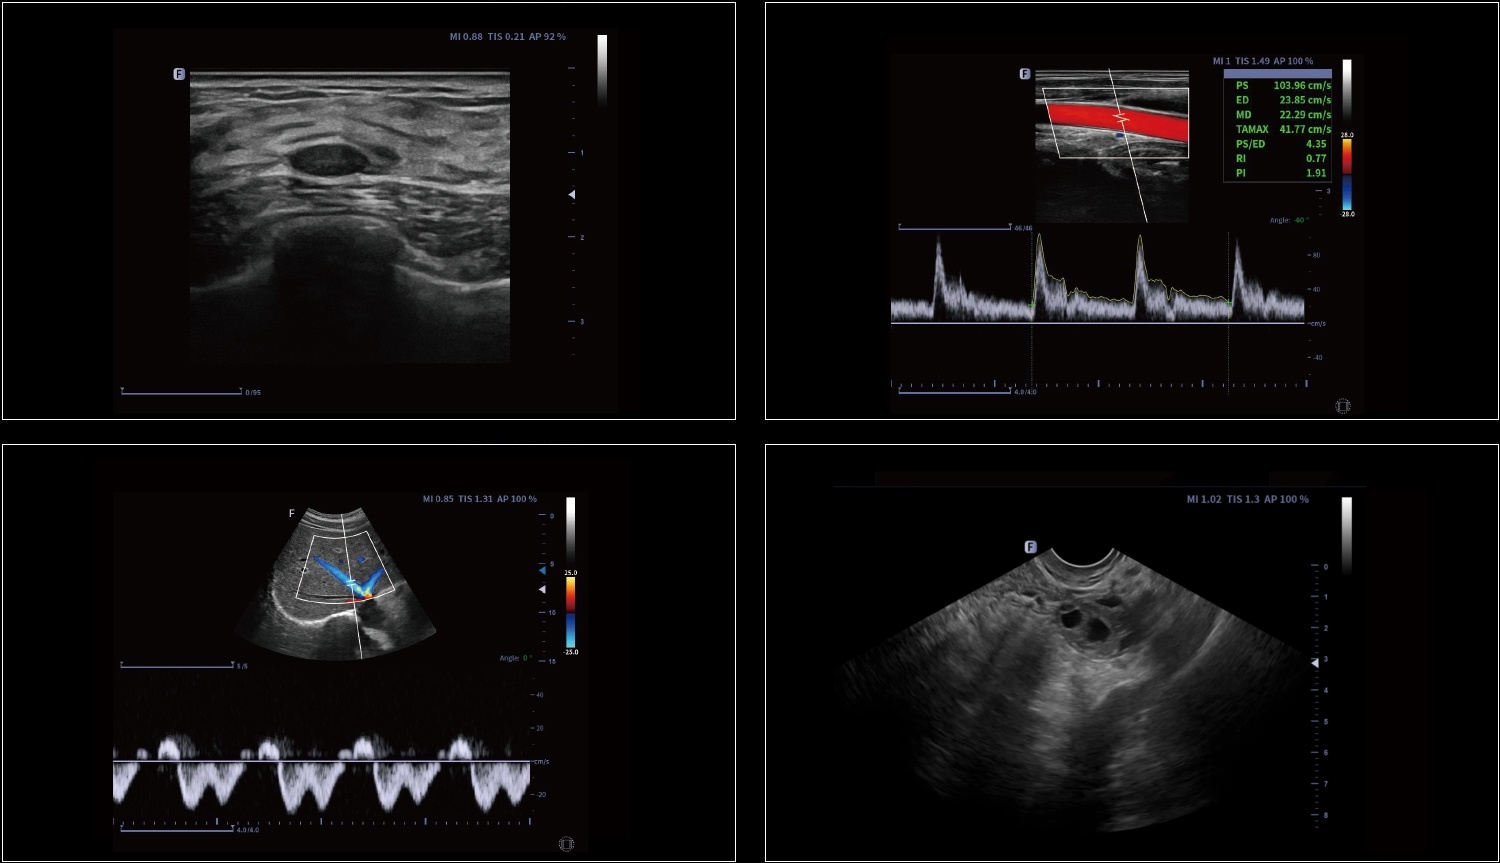

Mierzenie powierzchni naczynia krwionośnego, prędkość przepływu krwi może być automatycznie mierzona przez spektrum, a wyniki objętości przepływu krwi zostaną wyświetlone.

Automatyczna identyfikacja i pomiar grubości błony wewnętrznej i środkowej (intima-media). Możliwość pomiaru zarówno lewych, jak i prawych naczyń krwionośnych oraz ścian przednich i tylnych.